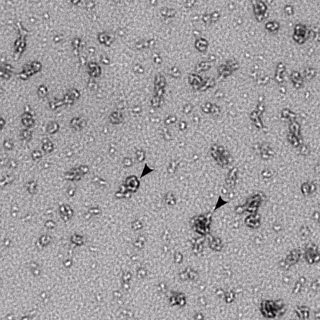

FLICKR/NIAID